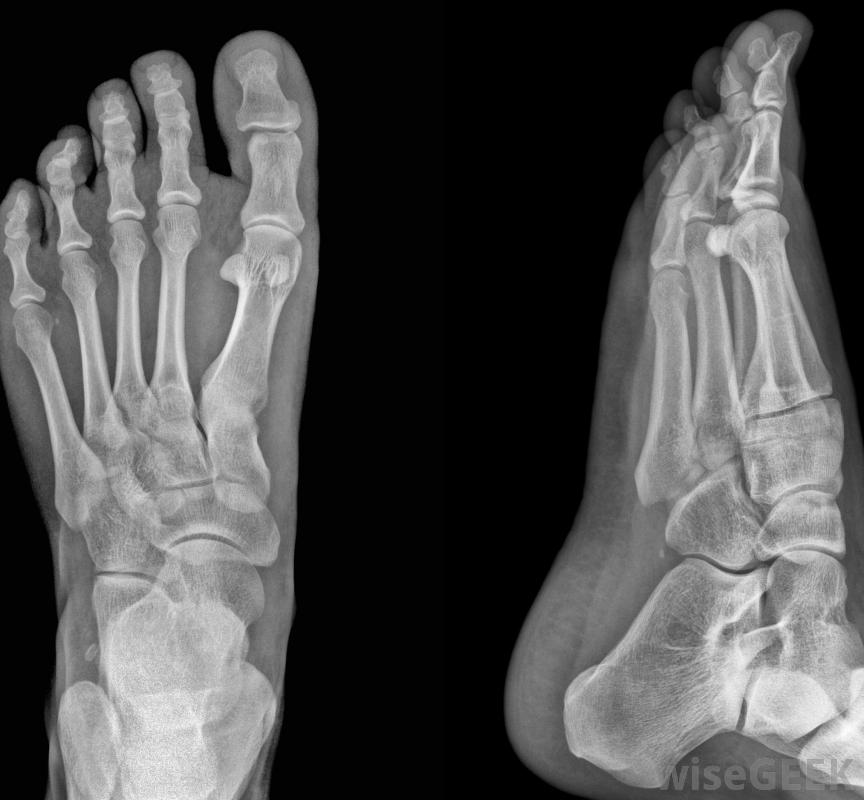

骨刺是一種不正常的骨性突出物,沿骨骼邊緣形成,是由炎癥引起的。當骨刺與鄰近的神經和其他骨骼摩擦時,通常會導致疼痛,也可能會限制活動范圍。骨刺也被稱為骨贅,可能發生在多個地方,通常在脊柱、肘部,治療方法也不盡相同,這取決于疼痛的嚴重程度和骨刺的發生部位。緩解骨刺疼痛的方法通常包括藥物、休息、物理治療,嚴重的情況下,手術。